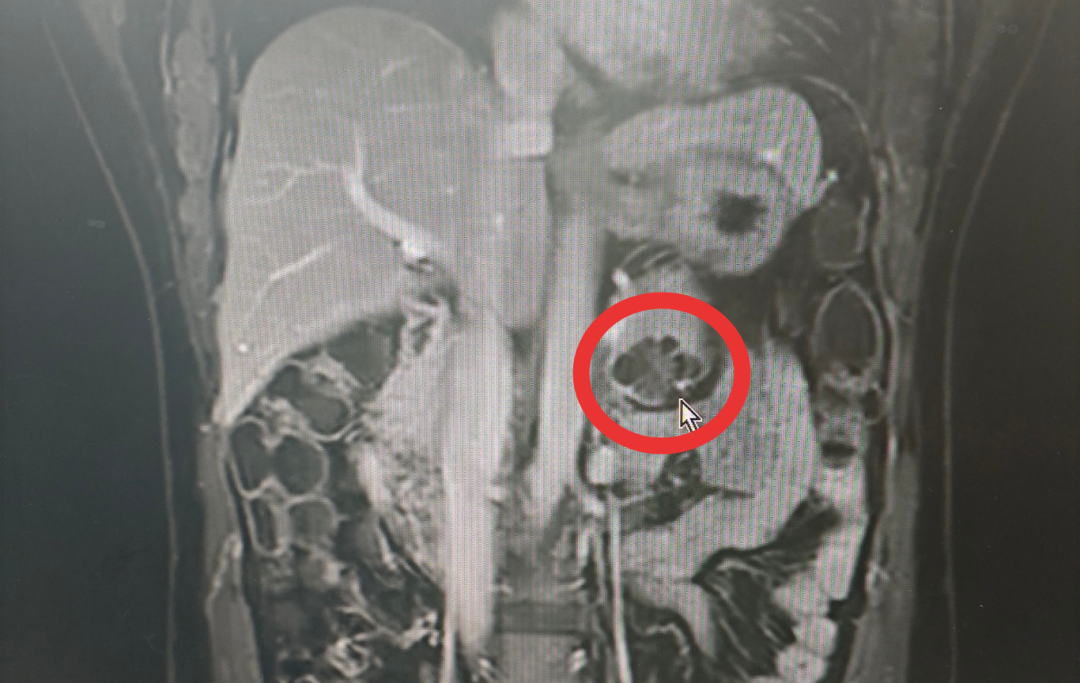

来到深圳市第四人民医院普通外科,检查结果指向胰体尾肿瘤。

胰腺和脾脏,是一对“好邻居”。胰腺尾部与脾脏的解剖关系图就像一根蘑菇:胰尾是“蘑菇茎”,脾脏是紧挨着的“蘑菇伞”。两者的血管紧密缠绕,共享血供。传统手术中,为彻底切除肿瘤、防止复发,医生常不得不将“茎”和“伞”一并切除。